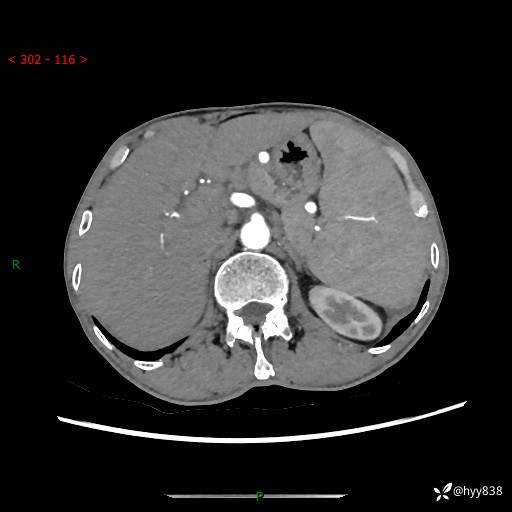

老年男性,脾大并脾脏弥漫粟粒状低密度,淋巴瘤 VS 肉芽肿 VS 血管瘤---结果公布

简要病史: 患者于3月前无明显诱因出现脾大,伴腹部轻微不适,具体不详,无腹痛、腹泻、腹胀,无头晕、头痛、乏力,无恶心、呕吐、呕血,无胸闷、气短、胸痛不适

上腹部CT平扫+增强